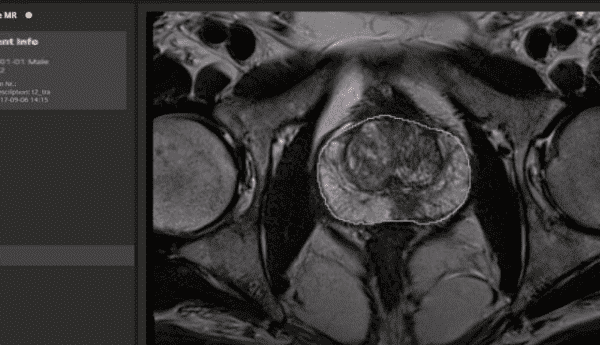

- Segmentação automática de órgãos e estruturas: Algoritmos de IA podem realizar a segmentação automática de órgãos e estruturas anatômicas nas imagens armazenadas no PACS, facilitando a análise e a comparação das imagens pelos radiologistas.

Segmentação automática de Tomografia com IA

Atualmente, as inteligências artificiais, já desempenham um papel fundamental na segmentação automática de órgãos e na elaboração de laudos médicos em radiologia. A segmentação automática permite que a IA identifique e delimite os órgãos e estruturas anatômicas em imagens médicas, o que facilita a análise dos radiologistas e a identificação de possíveis anormalidades. Além disso, a IA pode gerar laudos médicos com base nas informações extraídas das imagens, descrevendo suas observações e conclusões de maneira clara e concisa. Isso agiliza o processo de análise, aumenta a precisão dos diagnósticos e permite que os profissionais de saúde se concentrem em tarefas mais complexas e no atendimento direto aos pacientes.